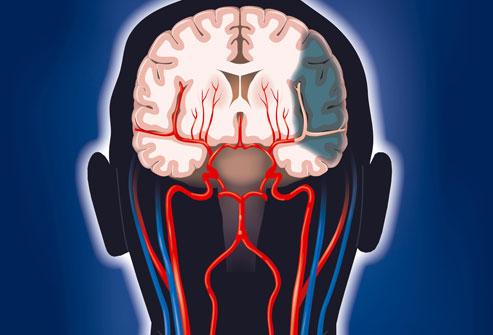

腦梗是一種常見的腦血管疾病,具有高發(fā)病率、高致殘率和高死亡率的特點(diǎn),腦梗是指局部腦組織因血液循環(huán)障礙,導(dǎo)致缺血、缺氧而發(fā)生的軟化壞死,本文將詳細(xì)介紹腦梗的各個(gè)方面,幫助讀者更好地認(rèn)識(shí)這一疾病。

腦梗,即腦梗死,是一種由于腦部血液供應(yīng)障礙導(dǎo)致的局部腦組織缺血、缺氧,進(jìn)而引起腦組織軟化及壞死,腦梗可分為腦血栓形成、腦栓塞和腔隙性梗死等多種類型。